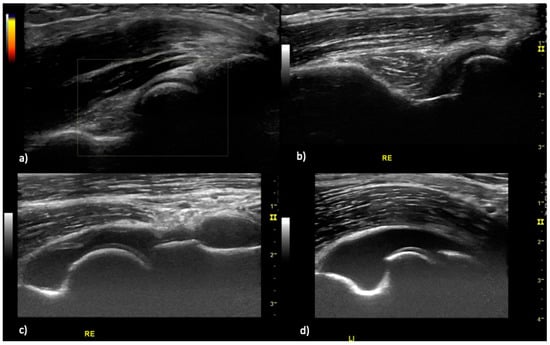

2.2. Ultrasound Examination

2.4. Definition of Elbow Joint Arthritis and Enthesitis